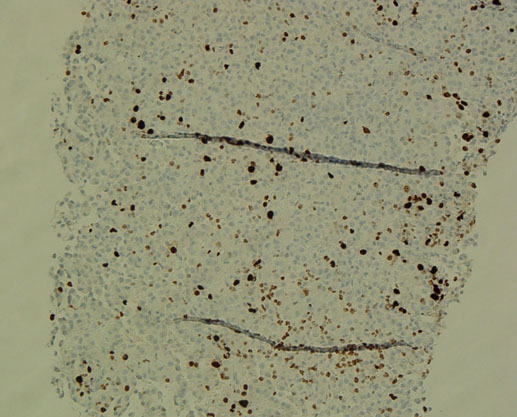

The patient was admitted to the hepatology inpatient service with consults from rheumatology, infectious disease, hematology, nephrology, pulmonology, and interventional radiology for a multidisciplinary approach to management. He underwent paracentesis followed by thoracentesis and an ultrasound guided peritoneal nodule biopsy. Turbid white chylous fluid (1200 mL) was removed from the left chest. The initial clinical impression from pulmonary was that the bilateral chylous effusion was likely secondary to superior vena cava syndrome and left brachiocephalic obstruction caused by lymphadenopathy. He was commenced on a low cholesterol diet and nutrition was consulted. Laboratory results from the first peritoneal tap showed atypical mesothelial cells indeterminate for malignancy (Figure 2). Subsequent thoracentesis (Figure 3) and paracentesis (Figure 4) specimens had higher cellular yield and revealed highly atypical mesothelial cells with high nuclear to cytoplasmic ratios and prominent nucleoli suggestive of malignant mesothelioma. Tumor cells were immunoreactive with Calretinin immunohistochemistry stain (Figure 5) which supported mesothelial origin rather than an epithelial origin (carcinoma). The diagnosis was further confirmed by an ultrasound guided peritoneal nodule biopsy which showed a consolidation of epithelioid tumor cells consistent with malignant mesothelioma, epithelioid type (Figure 6). Immunohistochemical staining of the omental biopsy for Ki 67 staining showed a high proliferative index > 10% (Figure 7). The tumor also contained foci of inflammatory cells including many plasma cells. These inflammatory cells could be reactive to the tumor or related to an underlying autoimmune or inflammatory process.

Figure 7: Omental core biopsy, Ki-67 stain, low.

Share Image: